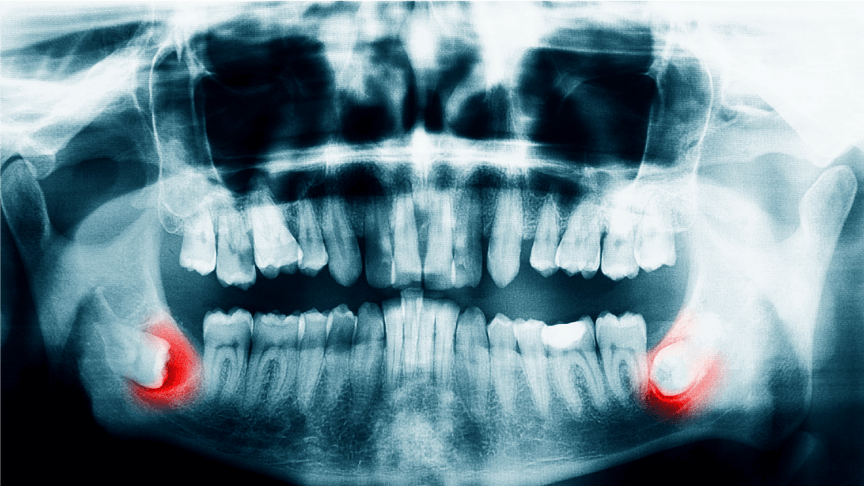

歯科口腔外科は、親知らずの抜歯から顎関節症の治療等、口腔(口の中)や顎(あご)、顔面に現れる病気の治療を行います。大きな手術が必要となった場合や、より専門的な治療が必要であると判断した場合は、当院の提携病院を紹介させていただきます。

親しらずの抜歯

親知らずは、大臼歯(大人の奥歯)の中で最も後ろに位置する歯で、前歯から数えて8本目の歯のことをいいます。一般的には20歳前後に生えてくることが多く、個人差があり生えてこない人もいます。斜めに生えたり、歯ぐきに埋まったりするなど、歯並びに悪影響を及ぼしたり、炎症や痛みがでたりする場合には抜歯が必要です。